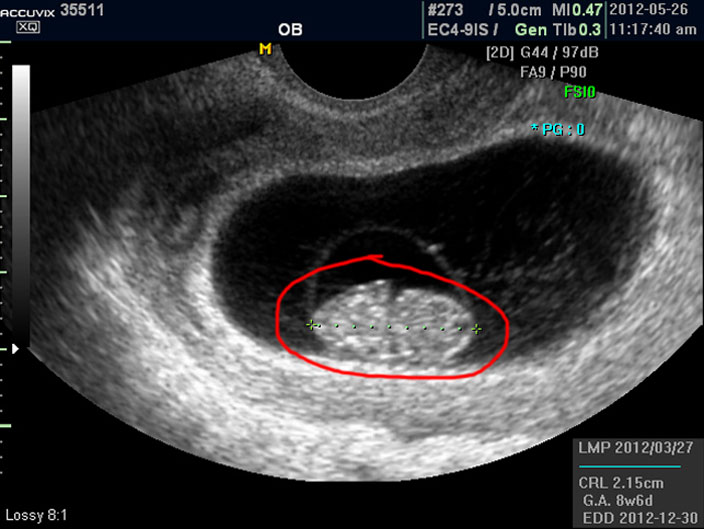

태아의 크기는 우측 하단에 실제 크기가 나와 있지만 아래 사진에서 빨갛게 표시한 부분의 안에 보이는 눈금이 1cm입니다.

이런 기준이나 지표들이 표시되는 것은 초음파 장비마다 조금씩 차이가 있고 위치도 다르지만 대개 비슷한 모양이라 한가지를 알면 다른 기종에서도 감상에 그리 어렵지는 않습니다.